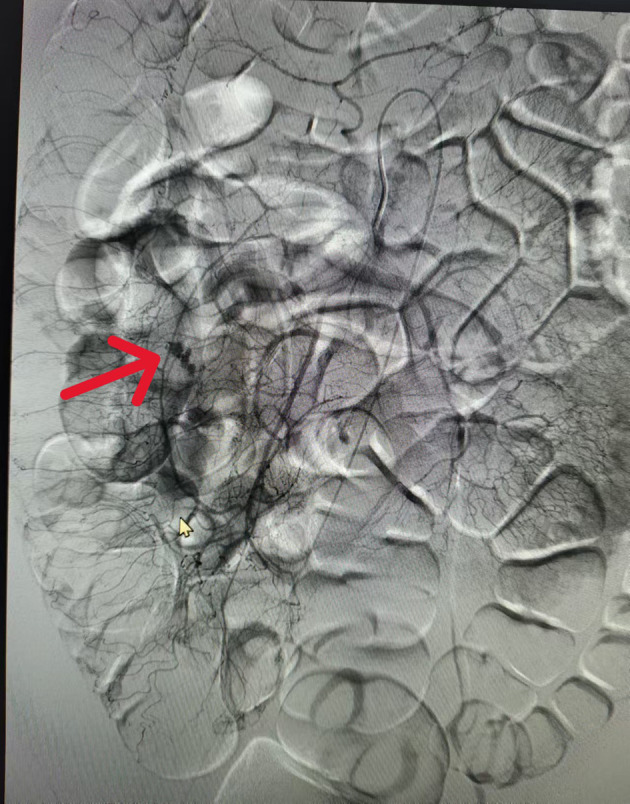

Meckel's diverticulum is one of the most common congenital anomalies of the gastrointestinal tract in pediatric populations worldwide. Although Meckel's diverticulum itself is usually asymptomatic, patients often present with complications such as gastrointestinal bleeding, Meckel's diverticulitis, intestinal perforation, and other associated symptoms. Notably, Meckel's diverticulum is relatively uncommon in adults, with cases complicated by acute massive gastrointestinal bleeding being particularly rare. We report the case of a 41-year-old man presenting with hematochezia for one day. Upon admission, his hemoglobin level dropped significantly from 98 g/L to 62 g/L within 24 hours. Contrast-enhanced computed tomography strongly suggested contrast media extravasation, indicating active bleeding. Subsequent gastrointestinal endoscopy, including colonoscopy, failed to identify obvious pathological findings. Mesenteric angiography successfully localized the bleeding vessels, but multiple embolization attempts were unsuccessful. The initial imaging and endoscopic modalities may not pinpoint the source of bleeding in this rare condition. Ultimately, a combined laparoscopic and endoscopic approach was employed, which successfully identified and localized the bleeding site in the Meckel's diverticulum. Laparoscopic intestinal resection was then performed, and postoperative pathological examination confirmed Meckel's diverticulum with ectopic gastric tissue. Meckel's diverticulum-induced bleeding in adults is severe yet rare, with nonspecific diagnostic features that often complicate timely identification. In managing the case of massive gastrointestinal hemorrhage, we achieved a successful outcome through combined laparoscopic intestinal resection and endoscopic surgery, with timely diagnosis and targeted intervention leading to complete recovery. This case underscores the critical role of a multimodal diagnostic and therapeutic strategy, particularly the integration of laparoscopy and endoscopy, in overcoming the challenges of nonspecific presentations. It serves as a valuable reference for clinicians, emphasizing that persistent diagnostic uncertainty in severe lower gastrointestinal bleeding should prompt consideration of rare etiologies like Meckel's diverticulum, and that a combined surgical-endoscopic approach can be pivotal in achieving definitive diagnosis and curative treatment.